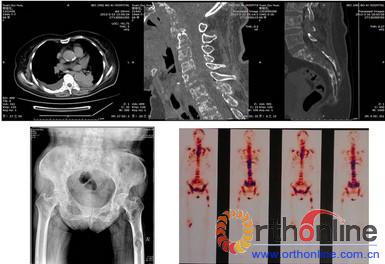

老年女性,因“颈背痛伴双上肢放射样疼痛8月,加重1月”住院。目前双上肢不同部位出现感觉减退,力量变化不大;尤其在坐 位和站立时颈痛和双上肢疼痛加重;病史中还了解到近半年体重下降了20斤。入院后进行检查,颈椎CT提示多节段颈椎骨质破坏,颈5-6椎体压缩变性;颈椎 MRI提示颈5-6变形的椎体压迫脊髓;肺CT发现左肺下叶占位性病变,纵膈心包转移,胸骨、肋骨破坏;腰椎CT提示T12椎体压缩骨折,骶骨破坏;骨扫 描提示全身多发骨性转移(脊柱,骨盆,股骨,胸骨,肋骨);肿瘤标志物(AFP,CEA)显著提高;碱性磷酸酶高,尿本-周氏蛋白:阴性;甲状腺功能检 查:正常;甲状腺抗体三项:正常;甲状旁腺激素测定:正常;血钙、磷:正常。综合分析初步诊断为:多发骨转移,肺癌可能大。